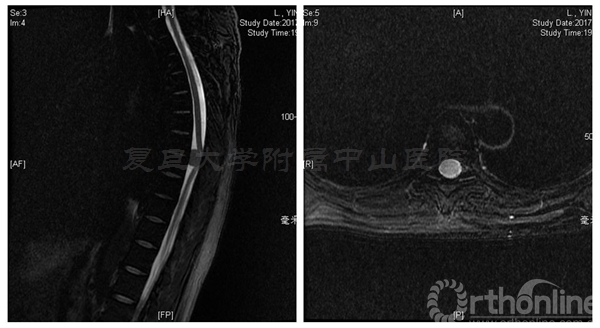

术前MRI:T7-8水平椎管内占位伴脊髓变性,脊膜瘤可能的大